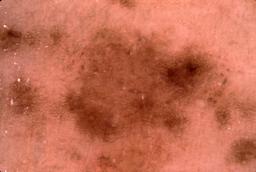

{

"age_approx": 65,

"anatom_site_general": "head/neck",

"concomitant_biopsy": true,

"dermoscopic_type": "contact non-polarized",

"diagnosis_1": "Benign",

"diagnosis_2": "Benign epidermal proliferations",

"diagnosis_3": "Solar lentigo",

"diagnosis_confirm_type": "histopathology",

"image_type": "dermoscopic",

"lesion_id": "IL_4880057",

"melanocytic": false,

"patient_id": "IP_6187403",

"sex": "female"

}